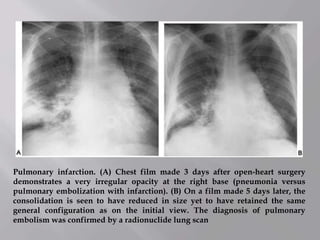

Pulmonary infarction. (A) Chest film made 3 days after open-heart surgery

embolism was confirmed by a radionuclide lung scan